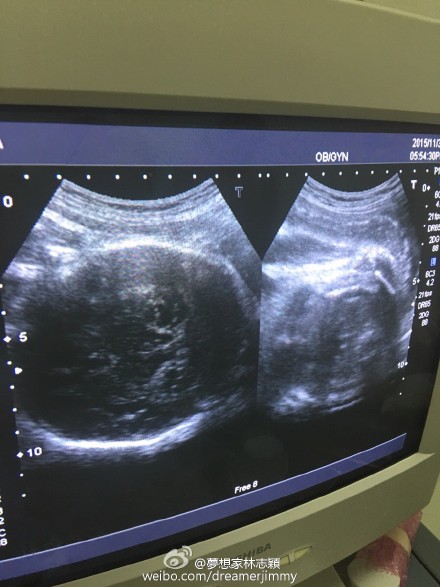

11月30日晚,林志穎通過微博曬出老婆的B超照,并給大家報平安,寫道:“陪老婆產檢,baby很健康!”

新浪娛樂訊 11月30日晚,林志穎通過微博曬出老婆的B超照,并給大家報平安,寫道:“陪老婆產檢,baby很健康!”此微博曝光后,網友紛紛留言囑咐要好好照顧老婆和兒子。

早前,林志穎為了慶祝微博粉絲破六千萬,公布妻子懷孕喜訊,并透露是雙胞胎,預產期是在12月,會在臺灣剖腹生產。近日,林志穎在微博曬快餐店的自拍照,透露是為孕妻買夜宵,并稱老婆特別能吃。(我是彌爾)